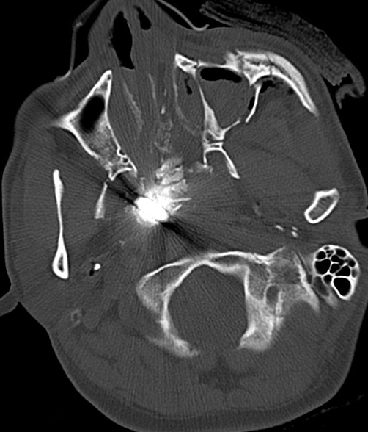

患者,男,31岁

外伤致左眼出血、疼痛4小时余入院

NS:神清,对答好,左侧眼内容物缺失,左上眼睑可见长约4cm外伤伤口,眼内可见金属异物,右侧瞳孔直径3mm,对光反射正常,眼前2m指数;四肢活动可,肌张力正常,生理反射存在,病理反射未引出。

2014-9-29 CT